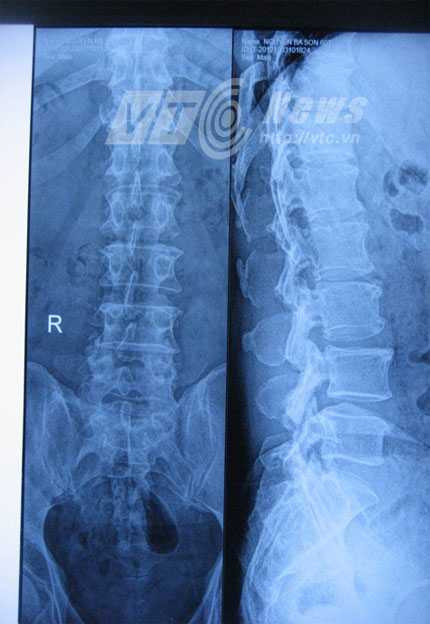

Hình ảnh cột sống của người bị đau lưng mãn tính.

Đi khám, bác sĩ cho chụp X quang và chẩn đoán chị bị thoái hóa đốt sống lưng chèn vào dây thần kinh nên ngoài việc lưng bị đau, chị còn bị đau chân. Chị đã dùng thuốc Tây nhưng không thấy đỡ, chị tìm đến thầy thuốc Đông y để vật lý trị liệu, xoa bóp, bấm huyệt.

PGS – TS Hà Kim Trung, Phó chủ nhiệm khoa Phẫu thuật Thần kinh, bệnh viện Việt Đức cho rằng: Với người bị thoái hóa cột sống cần được khám lâm sàng, chụp X quang từ đó có biện pháp điều trị nội khoa, vật lý trị liệu.